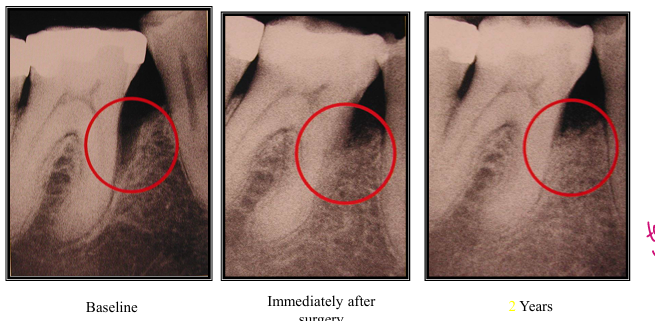

healing after bone grafting

-histologic studies in both humans and animals have often shown that healing after grafting procedures often results with a long JE rather than a new CT attachment

healing after GTR- _____ is necessary to confirm the formation of new bone, PDL, and cementum

-histology

when should the results of surgical procedures be evaluated?

-wait 8-12 weeks after procedures such as open flap debridement, modified widman flap, osseous surgery

-wait at least 6 months to evaluate the final result of grafting/GTR procedures